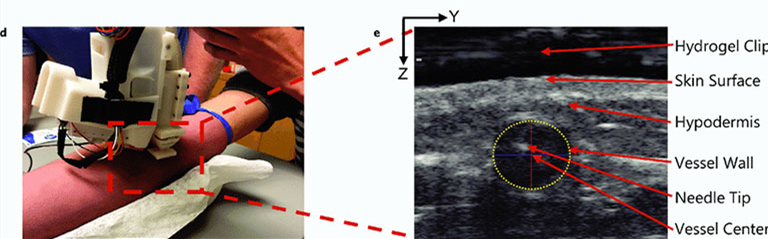

临床医生会进行以下设置:将机器置于对象的手臂进行定位,对目标区域进行消毒/擦拭,应用超声水凝胶并选择目标静脉的中心(如图所示)。然后,设备使用这些坐标来确定必要的运动学,以确保针尖在血管中心与超声成像平面相交。

(d)在研究过程中将器械放置在前臂上方。(e)超声图像显示成功静脉穿刺后目标血管中存在的针尖。血管壁由黄色虚线椭圆标识。图像中的Z轴表示容器深度,Y轴表示容器的矢状位。相对于超声换能器头(图像顶部)记录血管和针尖的位置。